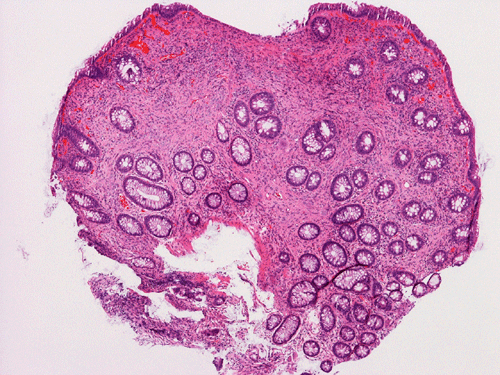

Clinical information The patient was a 54 year-old man. On screening colonoscopy, a small nodular polyp was found. The following are representative images from this polyp.

Pathology of the Case: The lesion is a small polypoid nodule of mucosa. At scanning magnification, there seems to be a mucosal flattening with erosion. There is focal reduction of glands and increased spacing in between glands (Panel A). Mucin production by the glandular epithelium is normal and there is no inflammatory cell infiltration (Panel B). There is no epithelial proliferation. On the other hand, the glands seems to be separated by spindle cells reminiscent of peripheral nerve(Panel B). On high magnification, there are some large neuronal or ganglionic appearing cell clusters in the lamina propria (Panel C). These neural tissue and ganglionic cells are positive for S100 protein (Panel D and E).

DIAGNOSIS: Solitary ganglioneuroma of colon.